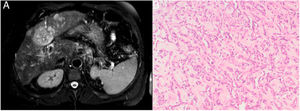

Description of the caseA 64-year-old male with heavy alcohol consumption, previous spontaneously resolved HBV infection but no occupational exposure risk factors, was admitted to hospital for hematemesis. Blood tests were as follows: hemoglobin 15.3g/dL (13.5–18); platelet count 51000/μL (150000–400000); international normalized ratio (INR) 1.44; bilirubin 2.91mg/dL (0.2–1.0); albumin 2.4g/dL (3.2–4.8); aspartate aminotransferase (AST) 76U/L (10–34); alanine transaminase (ALT) 51U/L (10–44) and γ-glutamyl transpeptidase (GGT) 254U/L (11–50). Urgent upper gastrointestinal endoscopy showed bleeding from esophageal varices, which was controlled with rubber-band ligation. An abdominal ultrasound examination was consistent with cirrhosis and it also showed multiple nonspecific hepatic nodules. Multiphase computerized tomography (CT) and a magnetic resonance (MRI) imaging revealed multifocal and isodense hypovascular masses in precontrast images. In some lesions, peripheral enhancement was seen in the arterial phase. There was no definite washout (Fig. 1A). Due to these findings, inconsistent with hepatocellular carcinoma, the patient underwent percutaneous liver biopsy, revealing a diffuse infiltration by a vascular malignancy with a high degree of atypia and cellular pleomorphism (Fig. 1B), expressing CD31, CD34 and Factor VIII. A positron emission computed tomography (PET-CT) revealed multiple bone infiltration.

The diagnosis requires careful assessment of imaging findings and histological evaluation.5 Common imaging findings include rapidly progressive multifocal tumors and hypervascular foci on the late arterial phase. Large hypovascular regions are common. In cirrhotic livers, lack of tumor washout of hypervascular lesions argues against hepatocellular carcinoma and makes histopathological analysis mandatory. Histopathology may show different patterns of vascular channels and dilated sinusoidal or cavernous spaces. Tumor cells express CD34, CD31 and factor VIII-related antigen.1